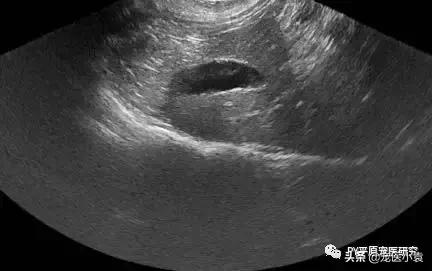

猫肝脂沉积症的症状诊断以及治疗建议

肝脏,中间是黑色的球形膀胱

IHL超声显示肝肿大伴肝实质改变(肝的内部解剖)。超声波也可能显示胰脏发炎(胰腺炎)。